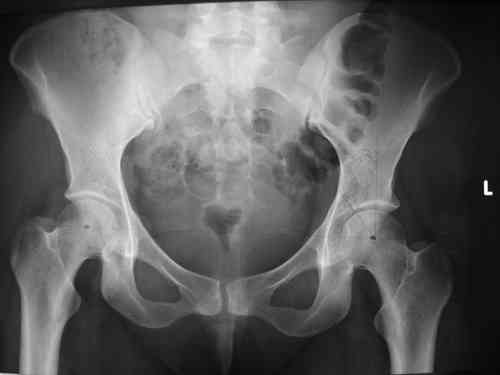

Спасибо за клинические примеры и комментарии. Если честно то просто восхищен представлеными R-ммами (классно сделали!!!). По поводу обсуждаемого больного: конечно КТ и дополнительные R-ммы сделаем. Но хочу напомнить, что после травмы прошло более 6 лет, на сегодняшний день клинически еще и R-ки признаки нестабильности эндопротеза( как бедренного компонента так и чашки). Хочется определиться как делать в аппарате или одномоментно открыто. Лично я склоняюсь к аппаратному лечению на первом этапе.

прилагаю пример с такой же давностью травмы, репонировали аппаратом

задача непростая, если мало опыта в этом деле, подумайте еще раз